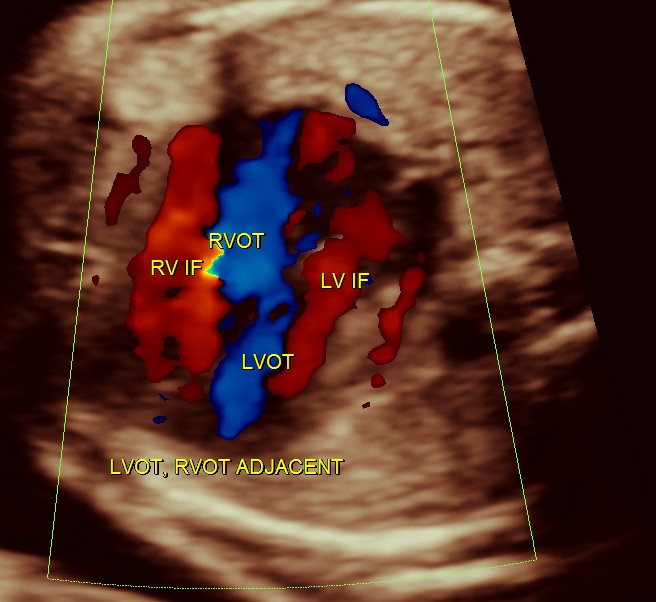

generally colour flow imaging is not said to be very helpful

the following 3 D reconstructed image shows the parallel flow of the great arteries

THE DIAGNOSIS OFFERED WAS TRANSPOSITION OF GREAT ARTERIES WITH VENTRICULAR SEPTAL DEFECT